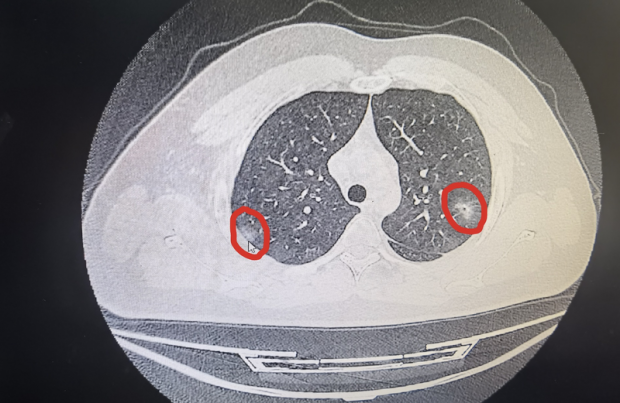

肺内结节通常在 ct 扫描中被检测为肺上的"白点"或"阴影",其形状为

阳康后肺部有白点?